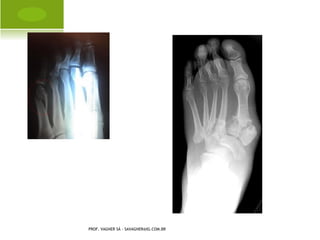

P OLIDACTILIA

H ÁLUX VALGO A DQUIRIDO

A MPUTAÇÃO C ONGÊNITA P É

S INDACTILIA P É